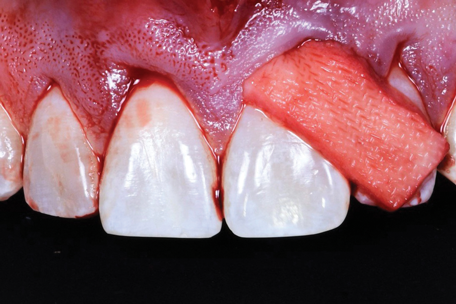

(7.) Intraoperative view of the maxillary arch after the frenectomy anterior tunnel sulcular access channel flap design was performed.

Figure 7

Given the importance of anterior esthetics as well as the clinical need for root access to address the NCCLs, no single flap design would suffice to solve the dilemma of esthetics versus root access in this case. And the presence of the patient's prominent midline frenum only added to the challenge of managing flap tension. Therefore, the proposed solution was a frenectomy anterior tunnel sulcular access channel approach. In this approach, a frenectomy procedure was performed to create a vestibular access point, followed by the creation of envelope flaps over the posterior teeth with gingival recession. This approach accomplished three goals: safe tunneling of the mucoperiosteal flap over the incisors without the need for papillae reflection, simple flap release over the teeth with gingival recession to provide space for the soft-tissue graft, and establishment of an easy access point to position the graft over the roots (Figure 7). Keeping the papillae between the incisors intact solved the esthetic concerns of the case, and the envelope flaps over the posterior teeth would permit the NCCLs to be reduced and smoothed with rotary instruments to provide a flat or concave surface for the graft material,10 which is very difficult or impossible with a tunnel flap. It is convenient that most NCCLs occur on posterior teeth5 because that allows an envelope flap for sulcular access and visualization to be incorporated with minimal effect on the esthetics. By combining a frenectomy with posterior envelope flaps for sulcular access, the frenectomy anterior tunnel sulcular access channel approach indeed creates a "channel" so that the soft-tissue graft can be placed over the roots from either direction and direct visual confirmation is possible to ensure proper placement (eg, no folding of the material, proper root coverage). If this approach was not used, one could imagine the challenges of properly placing the graft within a tunnel flap or through a single vestibular incision (Figure 8).